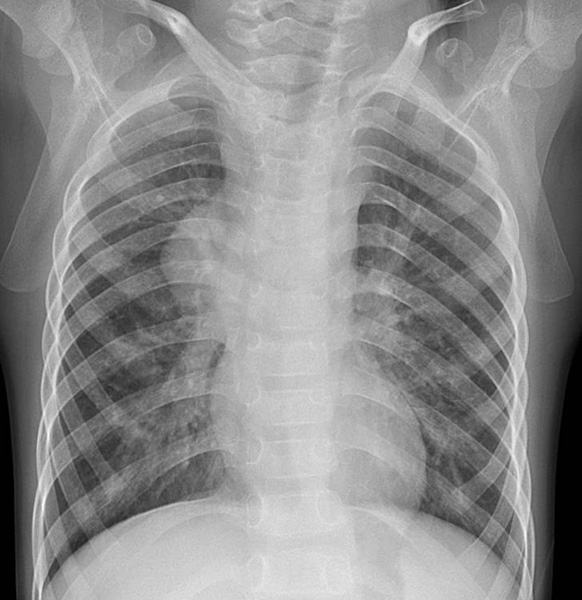

一般来讲,大部分患儿通过一张简单的胸片多能看到不同于正常的纵隔占位。如果发现患儿有相应的症状或检查发现纵隔存在异常占位,需要家长们及时带患儿至医院就诊,进一步完善影像学检查明确肿瘤的情况,手术切除或是取病理进行活检则是确定肿瘤性质的金标准。